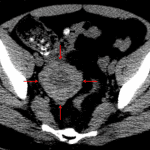

- 6 x 5.5 x 6.5 cm right adnexal structure with a thick hyperdense rim containing scattered hypodense foci and a hypodense center

- Ovarian torsion

Right adnexal structure which is favored to represent an enlarged ovary with a rim of hemorrhage, which can be seen with ovarian torsion. Recommend urgent pelvic ultrasound for further evaluation.